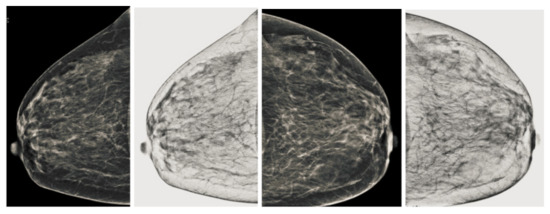

Figure 9.

Analysis of CC view of BI-RADS-2 mammogram images.

Figure 10.

Analysis of MLO view of BI-RADS-2 mammogram images.

We also measured the PSNR, the image contrast, and the EME of each category of databases, as we analyzed the image in terms of visual observation. The Table 3 shows the performance of our proposed image enhancement method. It can be seen from the Table 3 that our proposed method improved PSNR, contrast, and EME, and this also shows that our method can work on every category of BI-RADS. Because many techniques do not work on higher grade BI-RADS due to the complexity and the images are not of good quality. We obtained an average improvement in PSNR, contrast, and EME in the Table 4. For more observations, we analyzed the visual image of each category and we analyzed the CC and MLO of each category as shown in the Figure 7, Figure 8, Figure 9, Figure 10, Figure 11, Figure 12, Figure 13, Figure 14, Figure 15 and Figure 16. From the figures, every detail of image of every category can be observed, leading to better segmentation of the abnormal region. This image enhancement technique can be used as preprocessing steps for the detection of breast cancer. It is a very fast processing algorithm and it takes on 21.13 s. It gives opportunity to medical experts to analyze the mammogram images very quickly to propose the timely treatment.